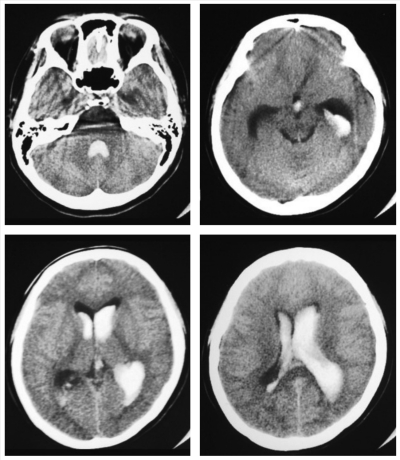

入院時の頭部 CT及び脳血管造影像を別に示す。